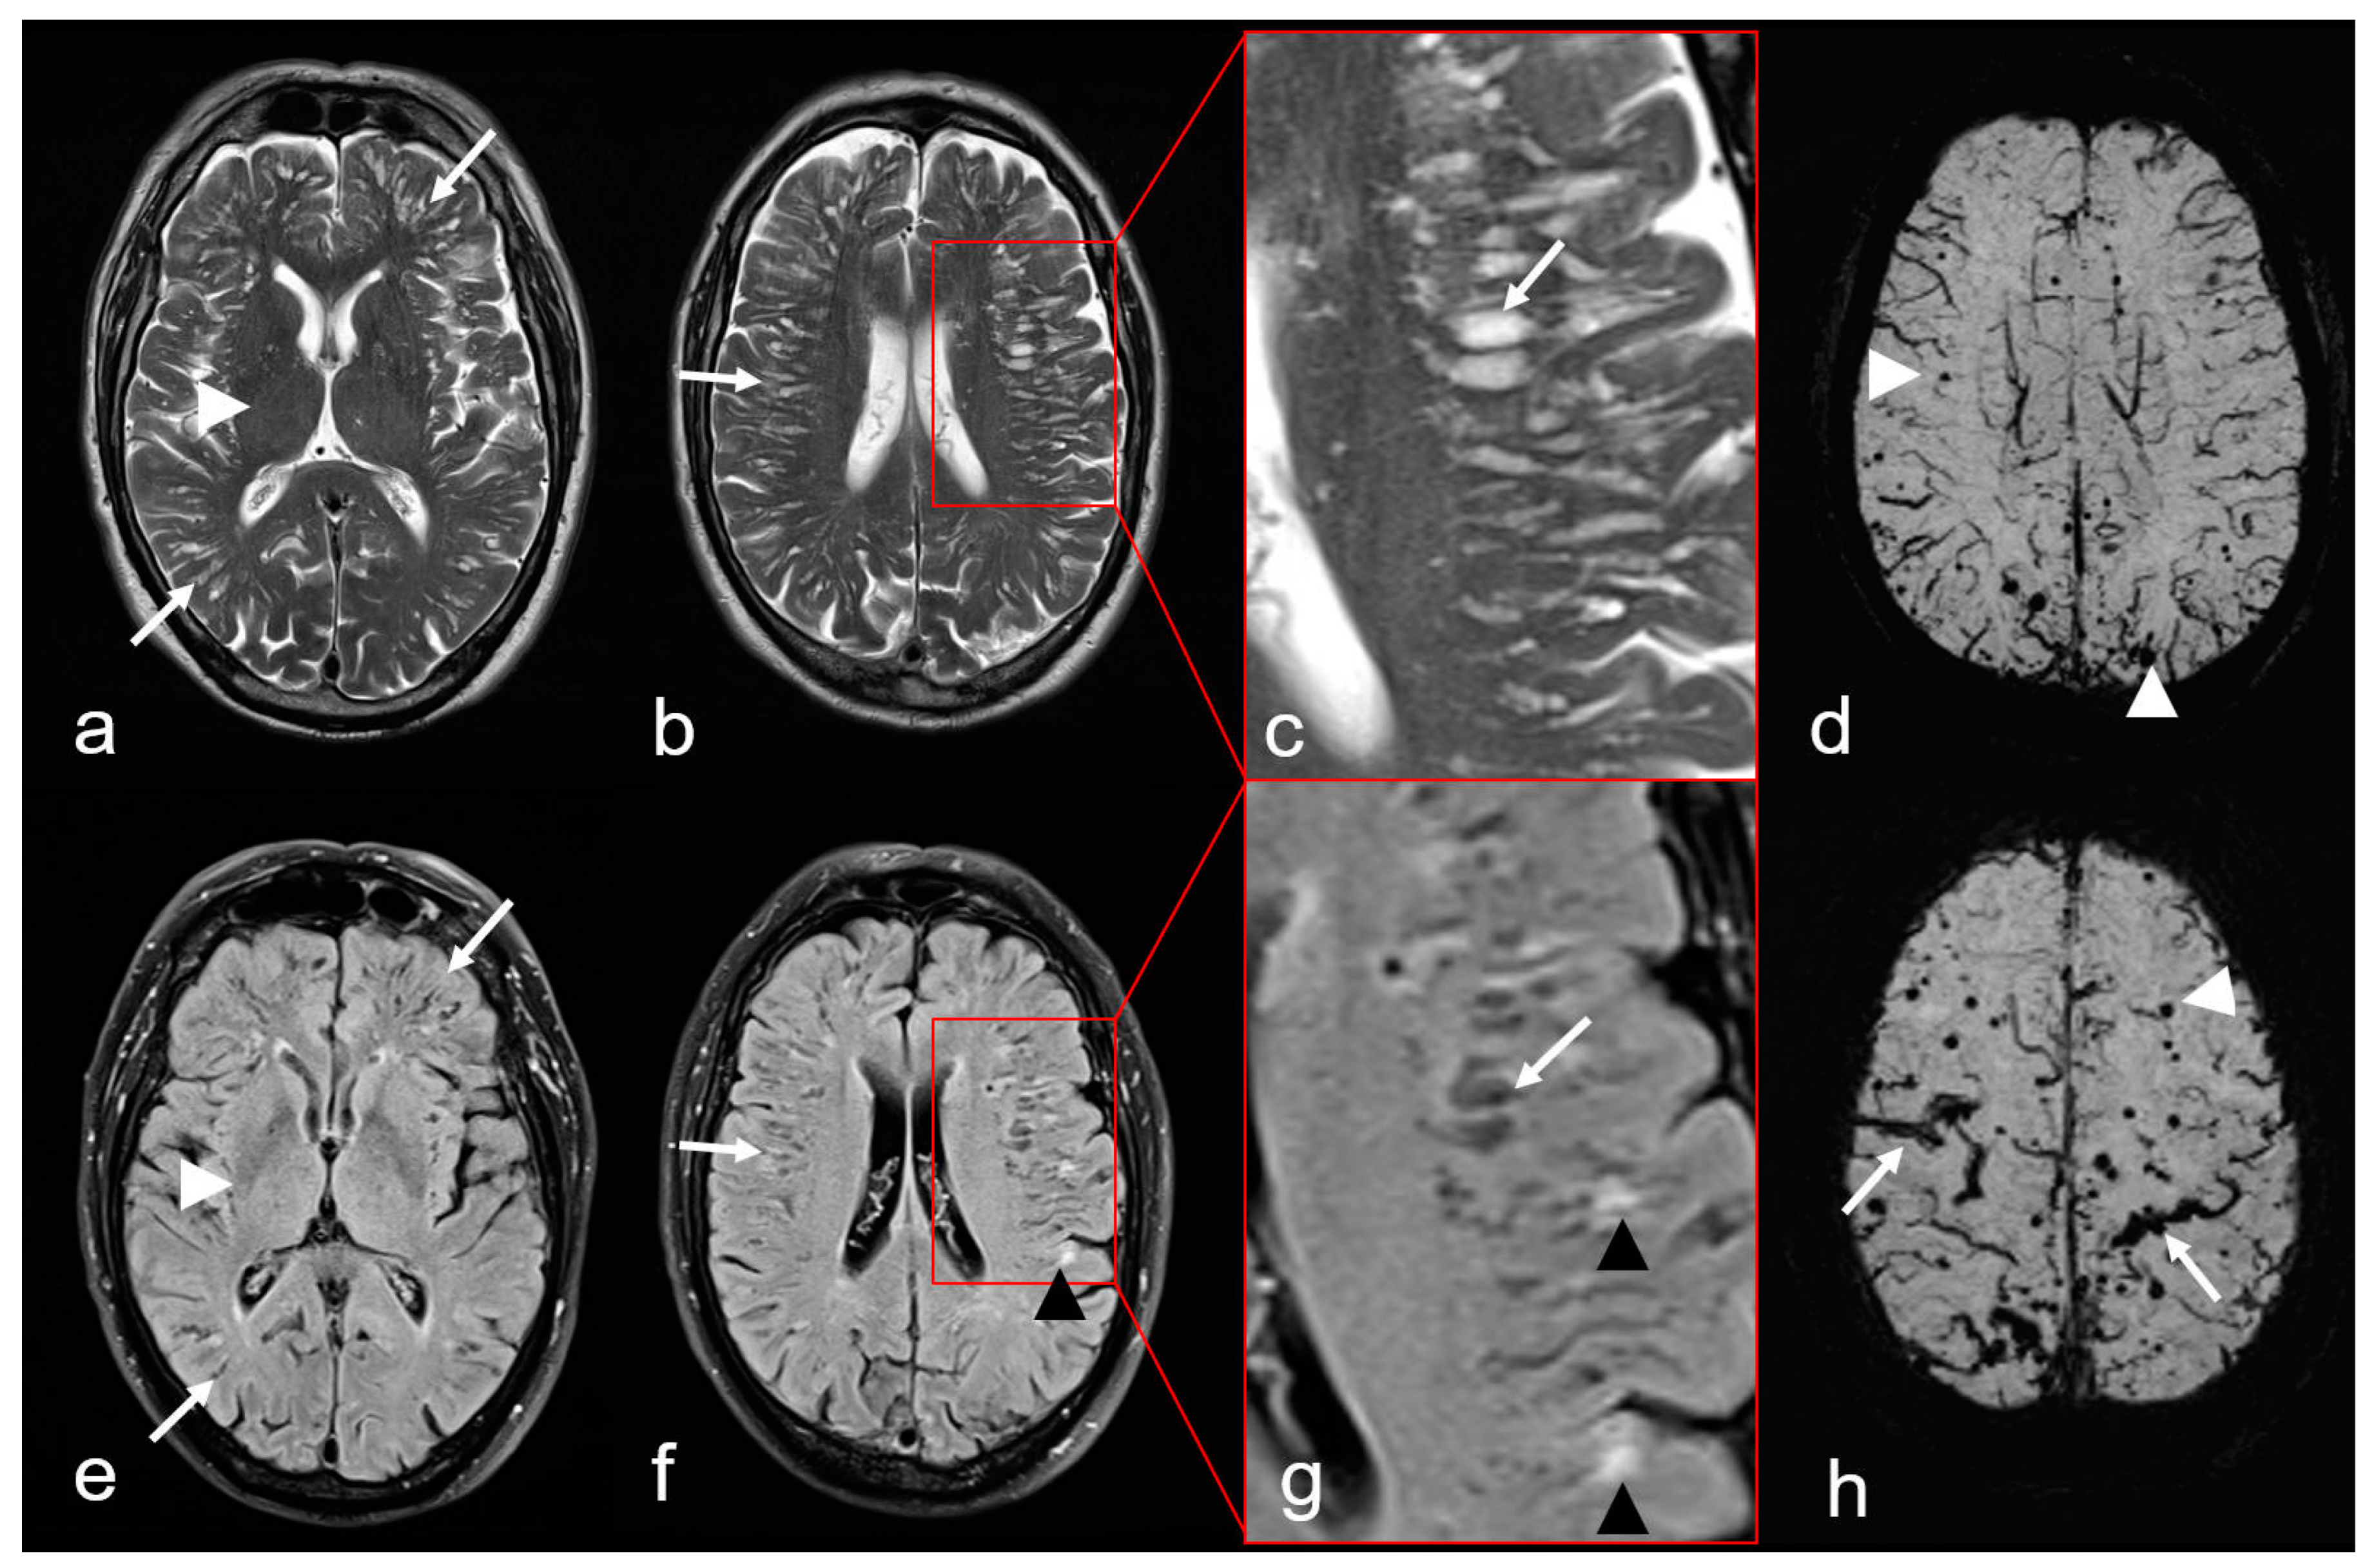

Figure 5.

Non-hemorrhagic and hemorrhagic MRI features in cerebral amyloid angiopathy (CAA). Severe enlarged perivascular spaces (PVS) supratentorial ((a–c): T2-weighted images (WI), arrow); (e–g): Fluid attenuated inversion recovery (FLAIR) images (arrow) sparing the basal ganglia ((a,e): white arrowhead), characteristic for a centrum semiovale (CSO) PVS pattern. (f,g): Multiple partially conflating white matter hyperintensities in a multispot pattern (black arrowhead, WMH-MS). (d,h): Susceptibility-weighted images (SWI) exhibit additional hemorrhagic lesions, i.e., multiple cortical/subcortical microbleeds (MB, white arrowhead) and multifocal cortical superficial siderosis (cSS; (h), arrow); MRI 1.5 T Intera, Philips Healthcare.